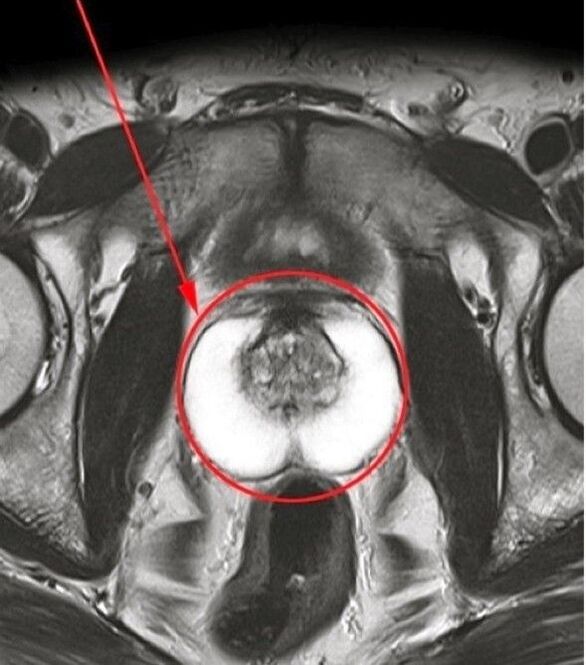

Ik wendde me tot de arts en begreep het belang van tijdige behandeling. Op basis van de resultaten van het onderzoek kreeg ik de diagnose chronische prostatitis. De specialist heeft aanbevolen dat ik een behandelingskuur onderga met een natuurlijk medicijn Predstonorm In capsules.